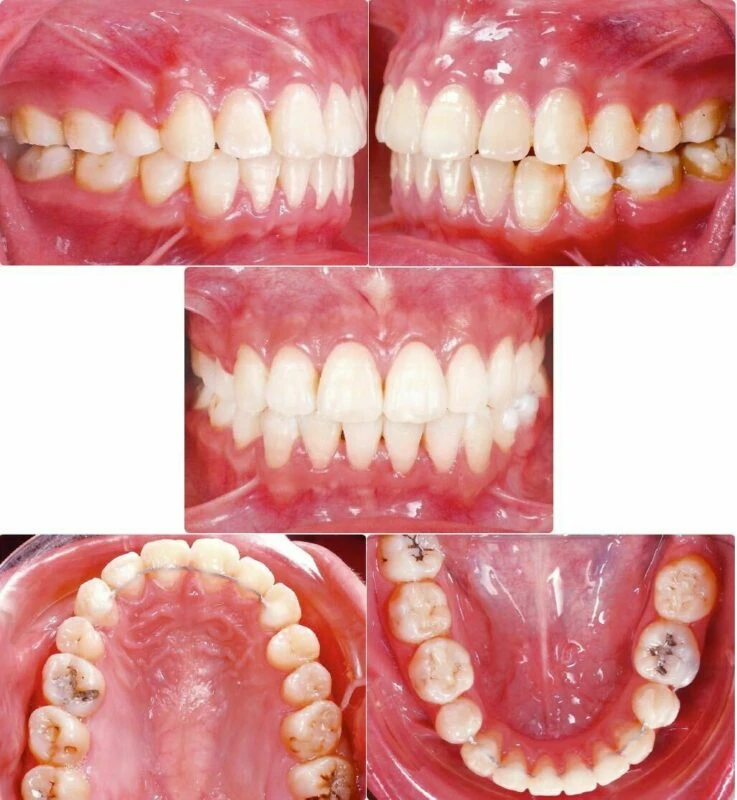

Bệnh nhân nữ trẻ, 24 tuổi được gia đình chuyển đến nha sĩ để tham khảo ý kiến (Hình 1) với lý do bị vẩu, các răng trước và rìa cắn các răng cửa dưới không đều (Hình 2-3). Bệnh nhân mong muốn giải quyết mà không phẫu thuật chỉnh hàm hoặc sử dụng minivis. Không có bệnh lý y khoa kèm theo nhưng bệnh nhân có tiền sử mất răng hàm nhỏ thứ hai ở hàm dưới bên trái và điều trị tuỷ không tốt ở cả hai răng hàm lớn thứ nhất bên trái. Khám lâm sàng ghi được tương quan răng hàm loại I bên phải, nhưng bên trái là loại III. Đường giữa răng hàm dưới lệch sang trái 2mm so với đường giữa mặt và hàm trên. Các răng cửa bên hàm trên bị lệch về phía khẩu cái cả hai bên.

Hình 2 Ảnh chụp trong miệng trước điều trị

– Xương: Tương quan xương loại I (SNA 85°, SNB 80°, ANB 5°), góc mặt phẳng hàm dưới lớn (SN-MP 41°)

– Mặt: Vẩu hai hàm, môi căng

– Răng: Tương quan răng hàm loại I bên phải và loại III bên trái. Đường giữa răng dưới lệch sang trái 2mm so với đường giữa mặt, góc răng cửa dưới so với mặt phẳng hàm dưới 91°, chen chúc răng dưới nặng (thiếu khoảng hơn 7mm), độ cắn chìa răng cửa là 7mm. Mất răng 35, răng 36 điều trị tuỷ không tốt. Các giá trị trên phim đo sọ được tổng hợp ở Bảng. Chỉ số lệch lạc DI của ABO là 25.